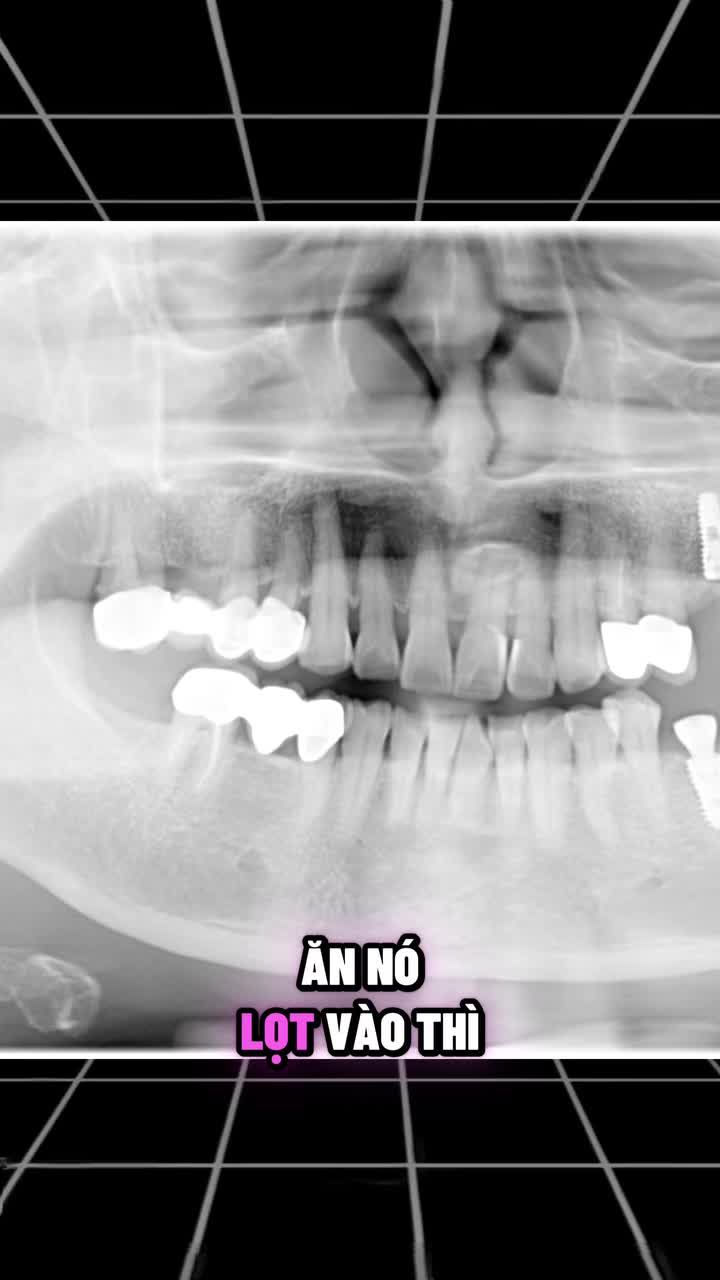

Bệnh nhân đến khám trong tình trạng: Xem thêm niềng răng Khớp cắn hở Chen chúc răng toàn hàm Cằm lùi, gương mặt kém hài hòaSau khi phân tích phim X-quang và đo đạc khớp cắn, Bs CKI Nguyễn Phương Thảo...